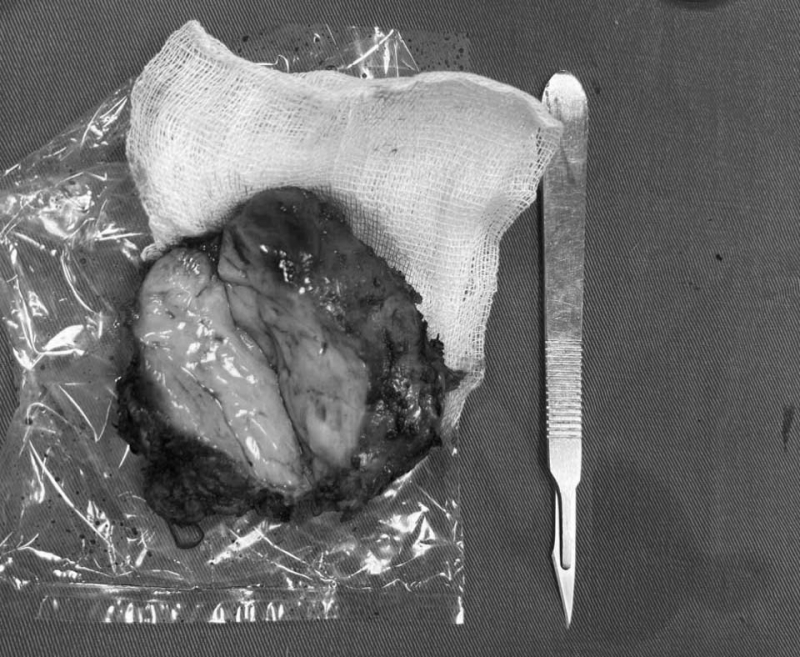

Nhận định vị trí u nằm sâu trong lồng ngực – nơi tiếp giáp nhiều cấu trúc quan trọng như hệ tĩnh mạch đơn, cột sống, xương sườn, nhu mô phổi, bó mạch thần kinh liên sườn, ống ngực, thực quản, nguy cơ chèn ép thần kinh; Khi u phát triển quá lớn gây xẹp phổi, tắc mạch, suy hô hấp…. Ekip phẫu thuật của BSCKII Nguyễn Mạnh Hùng – Trưởng Khoa Thần kinh – Lồng ngực, Bệnh viện Bãi Cháy đã tiến hành phẫu thuật nội soi lồng ngực điều trị cho bệnh nhân. Dưới sự hỗ trợ của các thiết bị phẫu thuật nội soi hiện đại, phẫu thuật viên đã tiếp cận được khối u kích thước khoảng 5x10cm, mật độ chắc kéo dài từ cột sống D7-D11. Sau 3 tiếng, ca phẫu thuật diễn ra an toàn, thành công cắt bỏ triệt để u trung thất sau, phổi nở tốt, không rò khí và không chảy dịch bạch huyết. 5 ngày sau phẫu thuật, bệnh nhân phục hồi sức khỏe tốt.

Hình ảnh khối u trung thất sau được cắt bỏ triệt để qua phẫu thuật nội soi

BSCKII Nguyễn Mạnh Hùng – Trưởng Khoa Ngoại Thần kinh – lồng ngực, Bệnh viện Bãi Cháy cho biết: “Khối u trung thất sau nằm ở vị trí đặc biệt khó tiếp cận, sát cột sống ngực từ D7-D11. U nằm sát tĩnh mạch đơn, bó mạch thần kinh liên sườn, xương sườn, cơ thành ngực sau, màng phổi xung quanh u có nhiều xơ dính, nhu mô phổi thùy trên dính vào thành ngực. Vì vậy, thao tác gỡ dính, phẫu tích u qua nội soi phải khéo léo, tỉ mỉ, chuẩn xác để tránh tổn thương các cấu trúc quan trọng như mạch máu lớn, thần kinh liên sườn, tủy sống, màng phổi…, đảm bảo phẫu thuật diễn ra an toàn, không xảy ra biến chứng nguy hiểm trước, trong và sau phẫu thuật như: tràn máu khí màng phổi, tổn thương mạch máu lớn, tổn thương ống ngực, thực quản, cột sống - tủy sống rễ thần kinh, nhiễm trùng, tổn thương khí phế quản, rò bạch huyết…